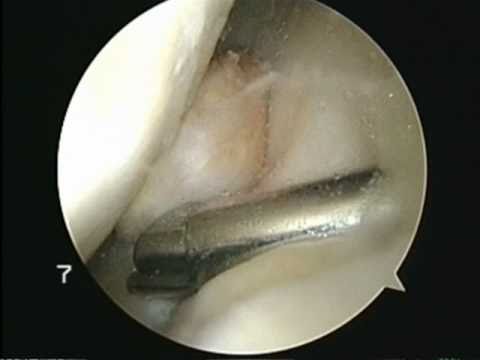

Pigmented Villonodular Synovitis Surgery by Dr HC Chang.wmv :

Pigmented Villonodular Synovitis (PVNS) :